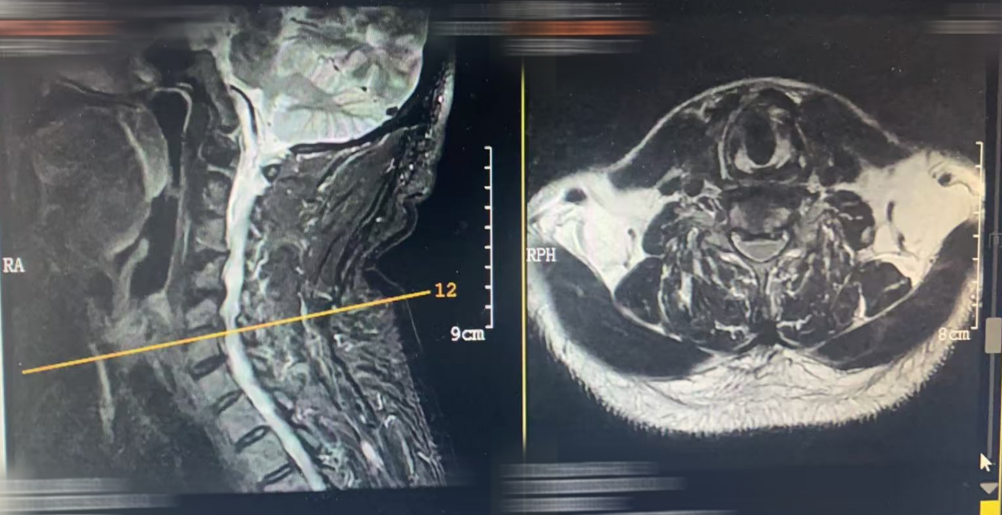

MRI

颈椎生理曲度变直,退行性改变,骨质疏松。

5-6椎间隙上下缘左缘少许终板炎。

3-4椎间膨出并突出;颈4-5椎间盘膨出并右后方突出;颈5-6椎间盘膨出,双侧椎间孔变窄,左侧为主。

CT

颈生理曲度变直,退行性改变。

2-3、颈3-4、颈5-6及颈6-7椎间盘不同程度突出。

4-5椎间盘轻度右后突出;

项韧带部分骨化;